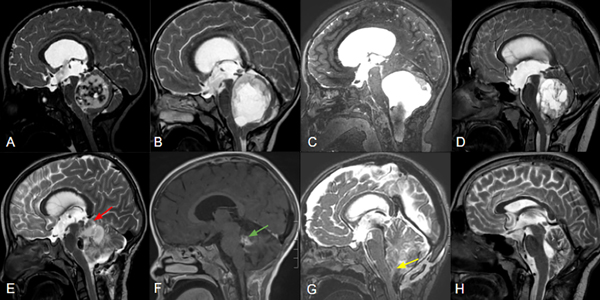

Figura 2. Cortes sagitales de RM de pacientes con APcs asociados a invasión troncoencefálica a distintos niveles: mesencefálica (A), pontina (B) y bulbar (C), con sus controles postoperatorios respectivos (E:G) señalando remanentes tumorales (flechas roja, verde y amarilla). La figura D demuestra una lesión predominantemente sólida y central que comprime pero no invade el tronco, la cual pudo ser completamente resecada (H).

El grado de resección se categorizó como resección total (RT), resección casi total (RCT), resección subtotal (RST) basada en la observación intraoperatoria del neurocirujano y RM con gadolinio postoperatoria analizada por especialistas en neuroimágenes (Figura 2). La RT correspondió a los casos en los que todos los hallazgos de imagen postoperatorios fueron negativos de acuerdo con la apreciación de los neurocirujanos. La RCT correspondió mayoritariamente a los casos en los que quedó un residuo tumoral mínimo < 2%, como en los casos de invasión del IV ventrículo, o cuando se consideró resección completa, pero aún se identificaron restos mínimos en la RM postoperatoria. RST, consecuentemente corresponde a cualquier resección que no alcanzaba los criterios anteriores.

Se incluyeron un total de 100 pacientes con un seguimiento medio de 53,9 meses (rango 12-156). El 54% de la población analizada era de sexo femenino y la edad media fue de 7,6 años. La localización más frecuente fue la central (64%), y 29% de los casos correspondió a lesiones sólidas. El 24% de los tumores se asoció con invasión del tronco encefálico o de los pedúnculos cerebelosos (Figura 2).

La resección completa sigue siendo el pilar del tratamiento y el principal factor pronóstico en la SLP o recurrencia1,3,10. Cuando se documenta RT en la RMN postoperatoria, no hay necesidad de tratamiento adicional y la tasa de supervivencia general a los 10 años es mayor al 90 %1,9. Sin embargo, las tasas reportadas de RT oscilan entre el 50 y el 89 %, siendo la causa más significativa de RST la invasión del tronco encefálico1,3,4. En nuestra serie, reportamos una tasa de RT del 67% comprobada no solo por la técnica micro neuroquirúrgica, sino también por RMN postoperatoria, lo que reduce las falsas consideraciones. El 96 % de los pacientes que no alcanzaron la resección completa tenían afectación del tronco encefálico, demostrando el 24 % de los tumores invasión del tronco encefálico o de los pedúnculos cerebelosos, en correlación con los resultados de la resección incompleta (Figura 2).